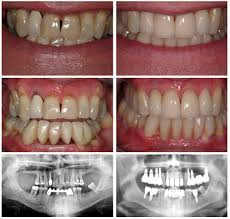

On average, dental crowns last between five and 15 years. This stage, during which a person has a combination of primary and permanent teeth, is known as the mixed stage. Crowns are still subject to fracture and cavities, so it is important to take extra care in brushing and flossing around crowned teeth to prevent them from needing replacement too often. How long does a dental implant last? Capped teeth should function and feel just like a natural tooth. How long will this last? By the time it came off taking the remainder of those teeth it was infected. This is because the current condition of the tooth you want to crown affects the life expectancy of your crown.

Because crowns should last at least five years, most insurance companies will pay if the crown needs to be replaced anytime after those first five years. Idk how long on the average fillings stay in but i reckon the extra care i practiced in the last six years to it cracking helped. The longest lasting tooth fillings: To make your dental crown last longer, you must avoid unhealthy lifestyles, such as teeth clenching or grinding, using. Some good quality dental crowns will last up to thirty years. This is because the current condition of the tooth you want to crown affects the life expectancy of your crown. 8 tips for healthy teeth. What can i expect after treatment? The teeth do not become weak because of grinding for a crown. Like that car, your teeth can last a lifetime and stay in good shape if you take care of them. Avoiding chewing or biting down on extremely hard items, like pen tips or pencils, and not opening things with your teeth. How long do caps on teeth last? By the time it came off taking the remainder of those teeth it was infected.